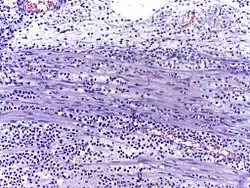

-

![Neutrophils are seen in a myocardial infarction at approximately 12–24 hours,[67] as seen in this micrograph.](./_assets_/Histopathology_of_neutrophil_infiltration_in_myocardial_infarction.jpg) Neutrophils are seen in a myocardial infarction at approximately 12–24 hours,[67] as seen in this micrograph.

Neutrophils are seen in a myocardial infarction at approximately 12–24 hours,[67] as seen in this micrograph. -